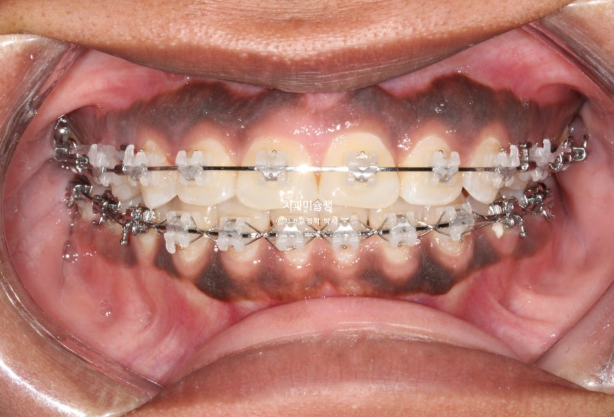

This patient is a foreign individual in their 20s who first visited us in July 2023 for orthodontic treatment.

The patient had previously undergone non-extraction orthodontic treatment but did not wear retainers, resulting in relapse of the anterior teeth. Due to dental caries, several teeth were subsequently lost, leading the patient to seek re-treatment.

In cases where a premolar is missing like this, if protrusion or crowding is present, we can proceed as if premolar extraction had already been performed. By extracting other compromised premolars and utilizing the extraction spaces, we can resolve crowding and protrusion simultaneously. This approach is advantageous, as premolar extraction is often indicated in such cases, and it eliminates the need for implants.

On the opposite side, there was a tooth that had undergone root canal treatment and had been temporarily restored. We decided to extract this tooth.

The patient opted for treatment using Clippy-C bracket orthodontics.

The treatment plan involves first closing the extraction spaces by retracting the protruded anterior teeth, followed by sequential intrusion of the supra-erupted molar.